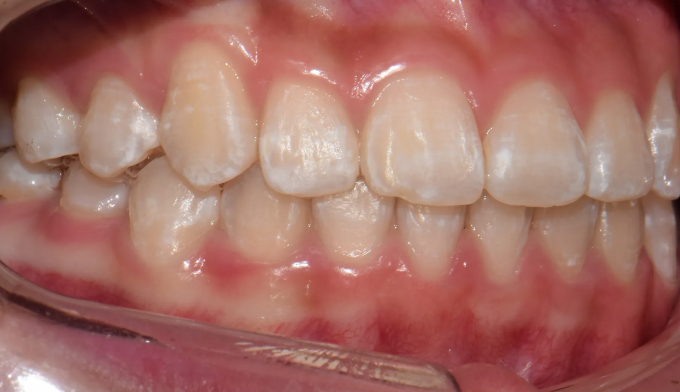

남아있는 공간을 최대한 활용하여 발치없이 치아를 배열해줍니다.

교정기간은 14개월 소요되었습니다.